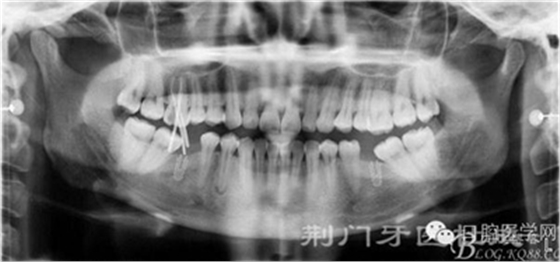

X線片

檢查:16齲壞穿髓,探(-)叩(+++),無松動(dòng),36 46 缺失,37 47 近中傾斜嚴(yán)重,44畸形中央尖牙體變色,叩(+),溫度測(cè)試無反應(yīng) ,18 28 38 48 萌出牙體偏頰

診斷:

1:16 根尖炎

2:44根尖炎

3:牙列缺損

4:18 28 38 48 異位萌出